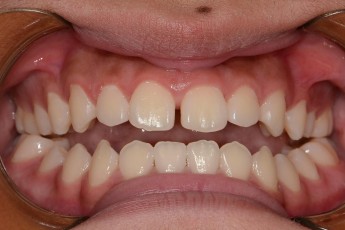

Before

After